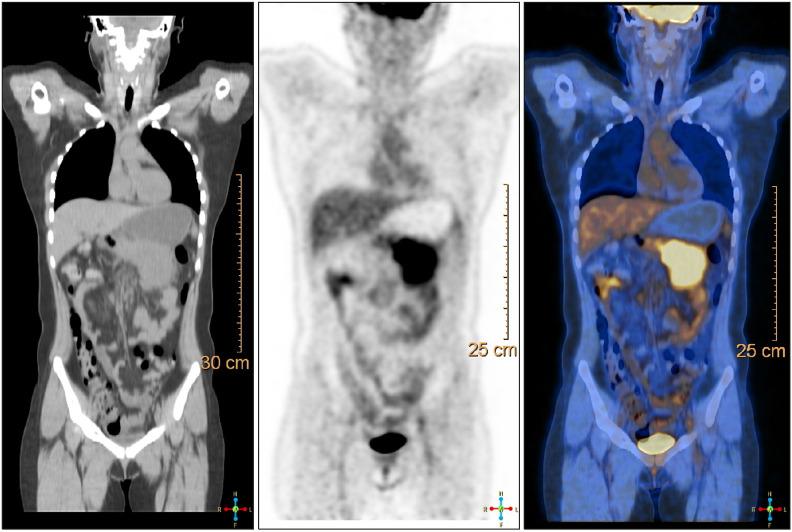

A 23-year-old Korean female presented epigastric pain of two-months' duration. She had a laparoscopic ovarian cyst excision 8 months previously. Clinical examination was normal. An abdominal computed tomogram (CT) demonstrated a 10-cm solid mass in the distal pancreas, with signs of splenic artery and vein occlusion, gastric and transverse colon invasion. Operative findings showed a mass involving distal pancreas, invasive to the posterior wall of the antrum of the stomach and transverse colon and 4th portion of the duodenum without lymph node involvement. The surgery consisted of a distal pancreatectomy, splenectomy and combined partial resection of the stomach, transverse colon and 4th portion of the duodenum. The immunohistochemistry and histopathological features were consistent with a confirmed diagnosis of intra-abdominal desmoid type fibromatosis (DTF). The prognosis of pancreatic DTF is not known and she showed no recurrence or distant metastasis during a 3 year follow-up. Herein we report a rare case with an isolated, sporadic, and non-trauma-related DTF, located at the pancreatic body and tail.

一名23岁的韩国女性出现了持续两个月的上腹部疼痛。她在8个月前接受了腹腔镜卵巢囊肿切除术。临床检查正常。腹部计算机断层扫描(CT)显示胰腺远端有一个10厘米的实性肿块,伴有脾动静脉闭塞、胃和横结肠受侵的迹象。手术所见显示肿块累及胰腺远端,侵犯胃窦后壁、横结肠和十二指肠第四部,无淋巴结受累。手术包括远端胰腺切除术、脾切除术以及胃、横结肠和十二指肠第四部的联合部分切除术。免疫组化和组织病理学特征与确诊的腹腔内硬纤维瘤病(DTF)一致。胰腺DTF的预后尚不清楚,在3年的随访中她未出现复发或远处转移。在此我们报告一例罕见的孤立、散发性且与创伤无关的DTF病例,位于胰体尾部。